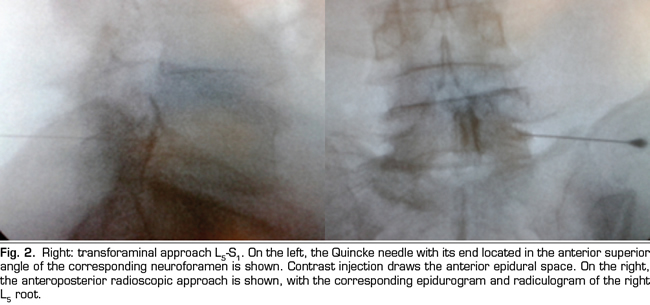

The final position of the needle in the oblique view was the subpedicular zone, while in the lateral view was the anterior superior angle or the roof of the neuroforamen, in the so-called safety triangle (Figure 2). The contrast volume injected was equivalent to the performed in the interlaminar group, obtaining a radiculogram and epidurogram after the injection (Figure 2). The solution of betamethasone was the same used in the interlaminar group, injecting the total volume of the solution in one or two levels, depending on clinical criteria.

The technical quality of the epidural steroid injection was evaluated in 21 out of 26 procedures performed with the parasagittal interlaminar approach. Anterior epidurograms, that is, achievement of the solution on the ventral epidural space, was obtained in 15 (71 %) of the patients (Figure 1 left); 17 (85 %) patients referred pain or paresthesia in the radicular territory during the injection, and a radiculogram was found in 12 (60 %) patients.